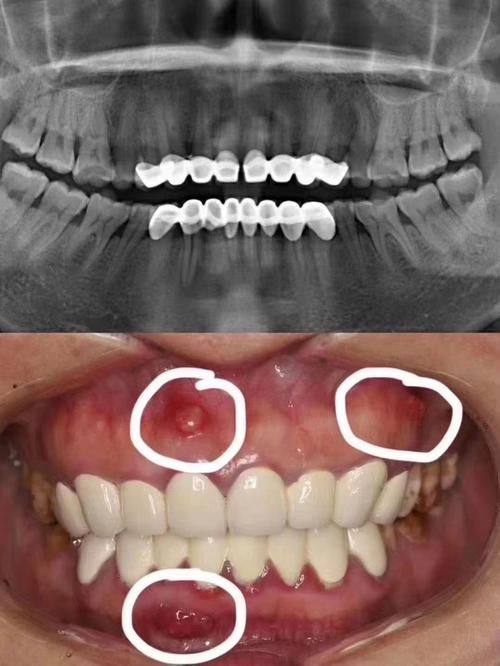

14. 牙周治疗:500 - 1500元

15. 口腔检查:50 - 200元

16. 口腔全景片:150 - 300元

17. 口腔CT:300 - 800元

4. 我因为牙周问题来到丽齿口腔。医生仔细诊断后,为我进行了牙周治疗。治疗过程中,医生手法轻柔,还向我讲解了特别多牙周保健知识。术后我的牙周状况得到了较大改善,不再出血和疼痛。这家医院的治疗成效和服务态度都让我十分认可。